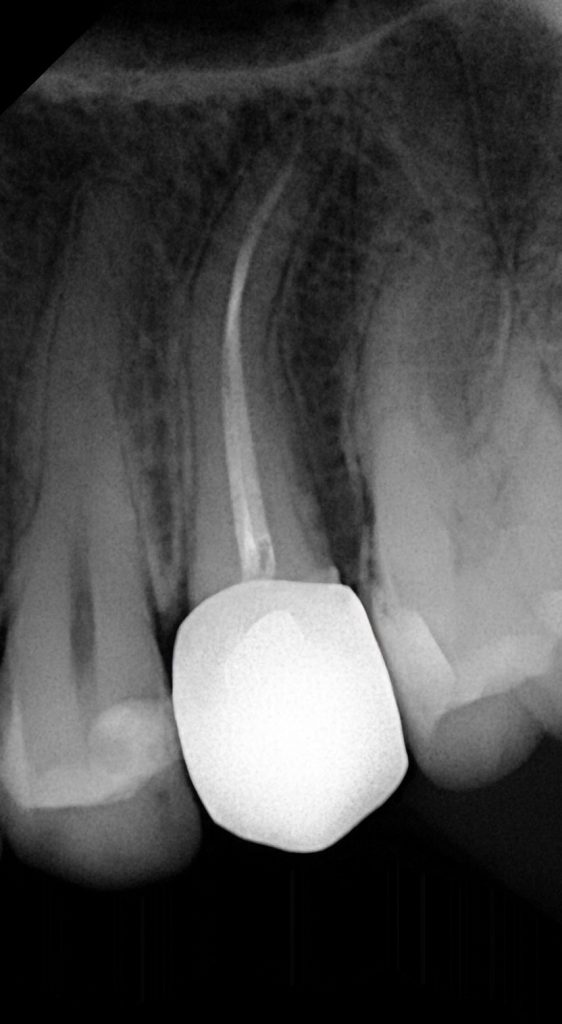

Adjacent molar showed proximal caries extending sub-gingivally. Caries removal was done conservatively, followed by Deep Marginal Elevation (DME) using the Matrix-within-Matrix technique with flowable composite and a sectional matrix system (Fig 4).

- Fig 5: Dentin replacement using GC EverX Flow.